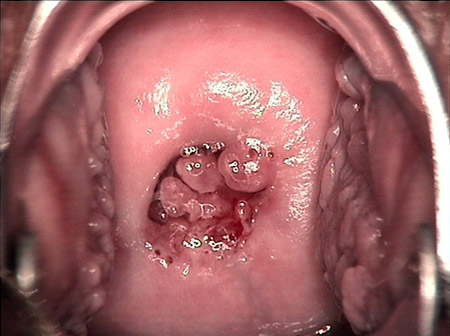

婦科leep錐切手術(shù) CIN2-3

CIN 2-3 修復(fù)后